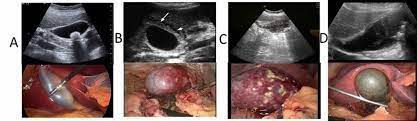

Acute cholecystitis refers to inflammation of the gallbladder. This sudden inflammation arises due to obstruction of cystic duct by a gallstone. Symptoms of acute cholecystitis include: - Right upper quadrant pain - Tenderness - Fever - Chills - Nausea - Vomiting The condition is diagnosed through ultrasound. Treatment is done via antibiotics followed by cholecystectomy. Reference: https://www.msdmanuals.com/professional/hepatic-and-biliary-disorders/gallbladder-and-bile-duct-disorders/acute-cholecystitis Image via: https://www.cureus.com/articles/46559-complicated-acute-cholecystitis-the-role-of-c-reactive-protein-and-neutrophil-lymphocyte-ratio-as-predictive-markers-of-severity